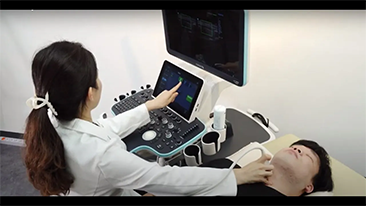

Mindray Resona General Imaging solutions help clinicians realize more accurate and efficient diagnosis and treatment results through comprehensive subdivision application probes and efficient clinical application tools.

Today's medical environment has become more complex, with an increased number of difficult cases and workloads.